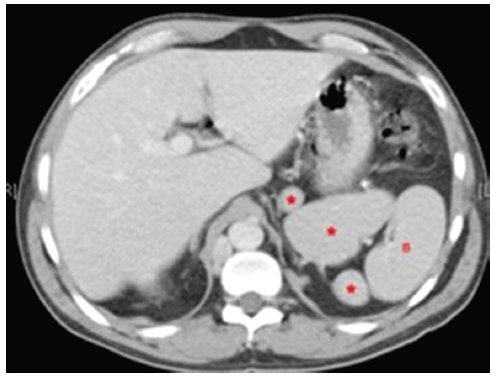

Bazo

La mayoría de los casos de síndrome de heterotaxia con isomerismo izquierdo se asocia a la existencia de múltiples bazos, de distinto tamaño pudiéndose encontrar en cualquier localización, pero más frecuentemente próximos a la curvatura mayor del estómago, como en los casos 1, 3 y 4 (Figs. 11 y 13). Esta estrecha relación está determinada por el desarrollo embriológico14.